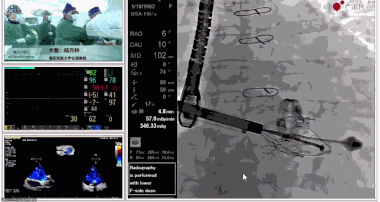

▲瓣膜植入后釋放的過程

▲瓣膜植入后三維超聲影像